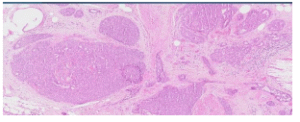

Fig 2. Multiple small keloid-like sclerotic bands seen intermingled amongst the epithelial proliferation

Introduction: Infiltrating epitheliosis (IE) of the breast is a complex sclerosing lesion rarely encountered in routine diagnostic practice. Histologically, all cases demonstrate florid usual ductal hyperplasia-like proliferation with irregular epithelial foci that appear to infiltrate into the adjacent scleroelastotic stroma. IE can easily be misdiagnosed as invasive carcinoma due to its infiltrative growth pattern and focal loss of myoepithelial cells. Most pathologists categorise IE in the radial scar/complex sclerosing lesion spectrum. Although association with

oncogenic PIK3CA 2,3 mutations has been found, its propensity to behave as a neoplastic proliferation is still

uncertain. It is currently regarded a florid hyperplastic entity requiring complete excision. Further studies are

needed to clarify its behaviour, association with carcinoma and its potential as a precursor lesion. Given its rarity and potential for misdiagnosis, recognising its subtle but distinctive features is essential. We report a case, aided by immunohistochemistry, that showcases these key histological features.